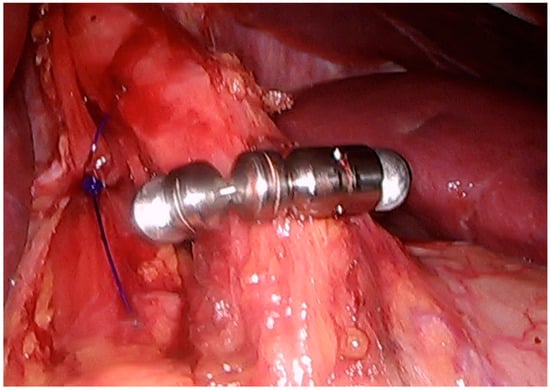

Magnetic Sphincter Augmentation